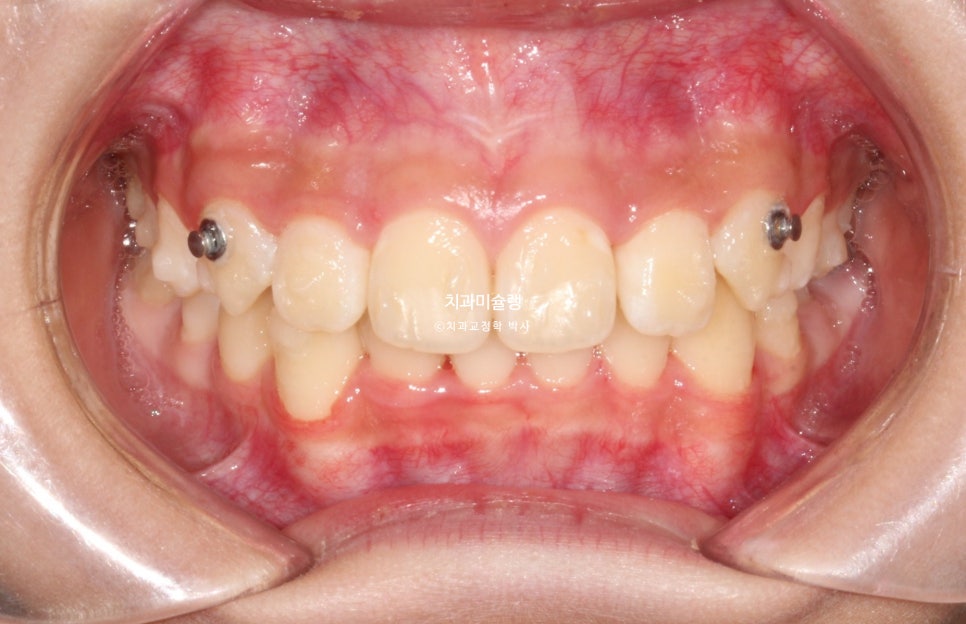

2025년 12월 – 치료 완료

1년반후 25년 12월, 겨울방학을 맞아 내원했고 이제 치료를 마무리 하기로 합니다.

고무줄을 잘 껴준 덕에 중심선은 정확히 맞아졌으며 깊게물리던 과개교합도 완전히 개선되었습니다.

어금니 교합관계는 양쪽다 1급을 달성.

과개교합, 중심선의 개선.

앞니 돌출의 개선

2급 교합관계가 1급 교합관계로 개선되었습니다.

송곳니가 유난히 뾰족하긴 하지만, 시간이 지나면 자연스럽게 마모되므로 어린 나이를 고려하여 따로 치아성형은 하지 않습니다.

앞니 돌출이 개선되며 미소가 예뻐졌습니다.